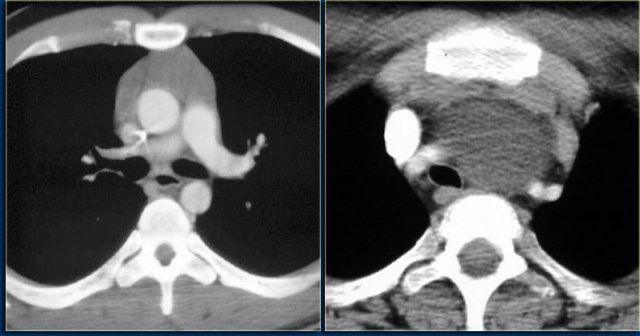

LEFT: Thymoma. RIGHT: Thymic carcinoma. LEFT: Thymoma. RIGHT: Thymic carcinoma.

Thymoma

Thymomas are common and account for 20% of mediastinal neoplasms.

Thymic carcinomas are extremely rare and acount for less than 1% of all thymic tumors.

The images show a thymoma on the left and a carcinoma on the right.

The thymic carcinoma has invaded the superior vena cava (arrow).